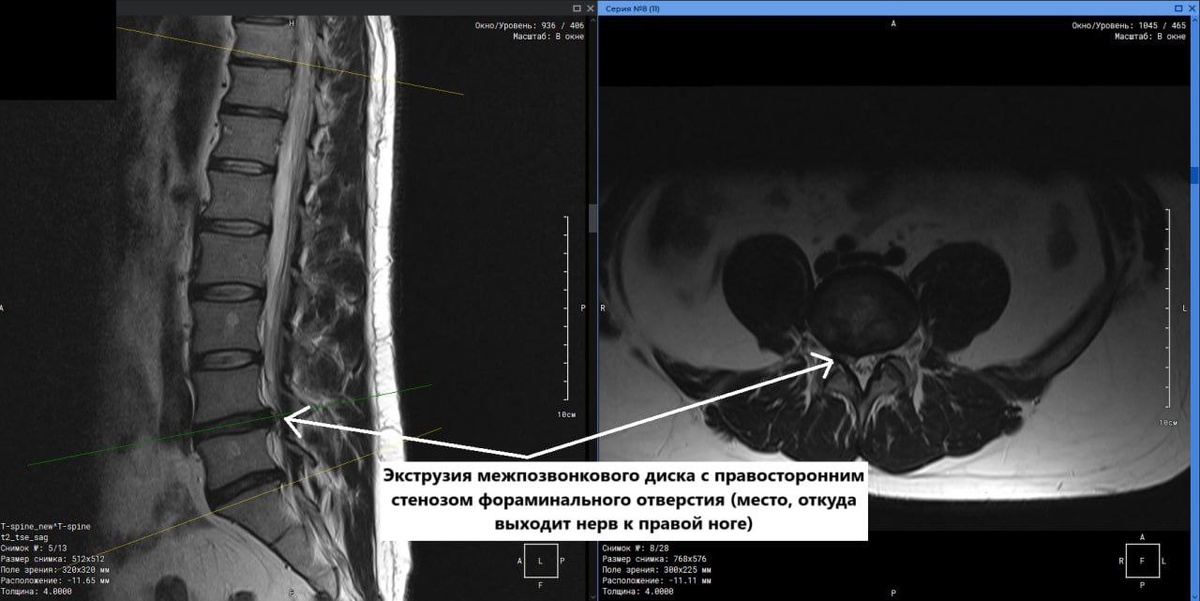

МРТ пояснично-крестцового-копчикового отдела позвоночника пациента 34 лет с жалобами на боль в спине и правой ноге

🩻Результаты МРТ поясничного отдела показало наличие экструзии диска между 4 и 5 поясничными позвонками с правосторонним фораминальным стенозом (пережатие отверстия, через которое выходит нерв к правой ноге), что и стало причиной боли в пояснице и правой ноге.

На представленных МРТ-снимках хорошо визуализируются описанные изменения.